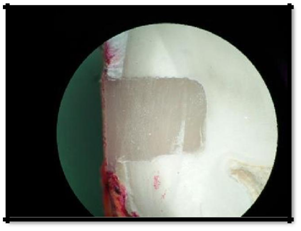

All the specimens were covered with two coats of nail varnish leaving 1 mm of the tooth-restoration margin and the root apices were sealed with modelling wax. The specimens were then immersed in 0.5% basic fuchsin dye (NICE Chemicals Pvt Ltd, India), in separate sealable glass vials (Borosil, India), at 37˚C for 24hours. After staining, the teeth were rinsed in water and dried using two-way syringe, the radicular parts of the teeth were then cut 4.5mm below the CEJ using diamond discs. Coronal portion of the teeth were sectioned buccolingually, in the approximate centre of the restoration (Figure 3).

Figure 3 Coronal portion of the teeth were sectioned buccolingually, in the approximate centre of the restoration.

Microleakage was assessed for both occlusal (enamel) and gingival (cementum) margins, using a stereomicroscope (Magnus) at original magnification of X16.